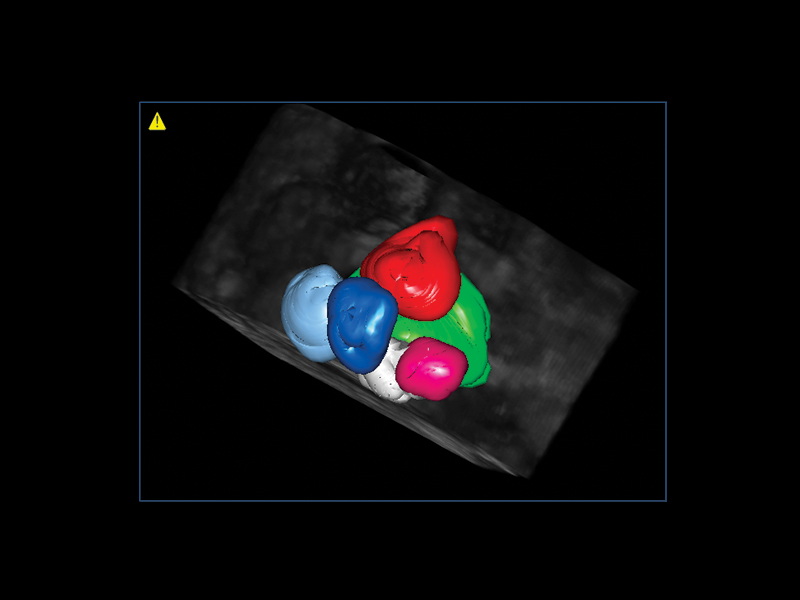

A standard examination very frequently highlights situations that need to be analyzed in greater detail. Esaote’s new volume rendering algorithm offers realistic three-dimensional reconstructions of the internal cavity of the uterus, within a few seconds, for evaluation of uterine shape and size. Thick Slice Imaging (TSI) 3D environment is particularly useful when the purpose is to highlight a well-defined and confined structure, such as the endometrium, allowing for a completely customizable concavity line.